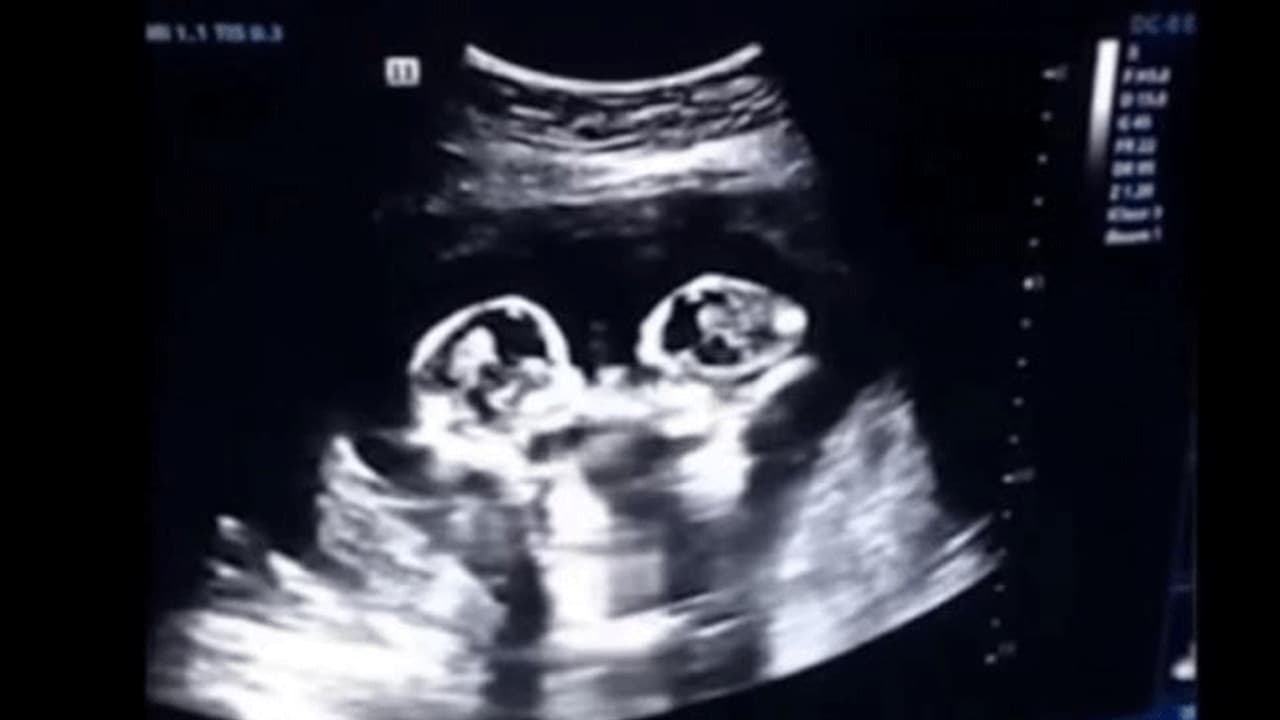

నమ్మసక్యంగా లేకపోయినా ఇది నిజం. చైనాకు చెందిన మహిళకు నాలుగో నెలలో స్కానింగ్ తీయగా.. అందులో కవలలు ఒకరిని మరొకరు కొట్టుకుంటున్నారు. దీనికి సంబంధించిన వీడియో ఇప్పుడు నెట్టింట షేక్ చేస్తోంది.

మహిళకు స్కానింగ్ చేస్తుండగా ఇలాంటి దృశ్యం కనపడటంతో ఆమె భర్త దానిని వీడియో తీశాడు. అనంతరం దానిని సోషల్ మీడియాలో పోస్టు చేశాడు. ఈ క్యూట్ వీడియో నెటిజన్లను తెగ ఆకట్టుకుంటోంది. కడుపులోనే ఇలా కొట్టుకుంటున్నారంటే.. బయటకు వచ్చాక ఇంకెలా కొట్టుకుంటారో అని నెటిజన్లు కామెంట్స్ పెడుతున్నారు.